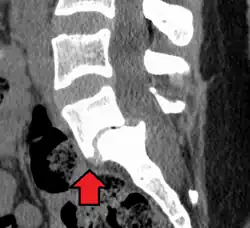

Смещение позвонка

Спондилолистез происходит от греческого слова spondylos (позвонок) и olysthesis (соскальзывание). Иными словами, спондилолистез — это смещение или соскальзывание позвонкa относительно нижележащего. Первое описание смещения позвонков приписывается Herbinaux, бельгийскому акушеру, который заметил выпуклость костной ткани, препятствующей родоразрешению. Сам термин был введён 1853 г. Н. F. Kilian.

Боковая рентгенограмма покажет степень смещения позвонка к нижележащему:

- Степень I — смещение до 25 %.

- Степень II — смещение от 26 % до 50 %.

- Степень III — смещение от 51 % до 75 %.

- Степень IV — смещение от 76 % до 100 %.

- Степень V развивается, когда позвонок полностью отделяется от соседнего позвонка (спондилоптоз).